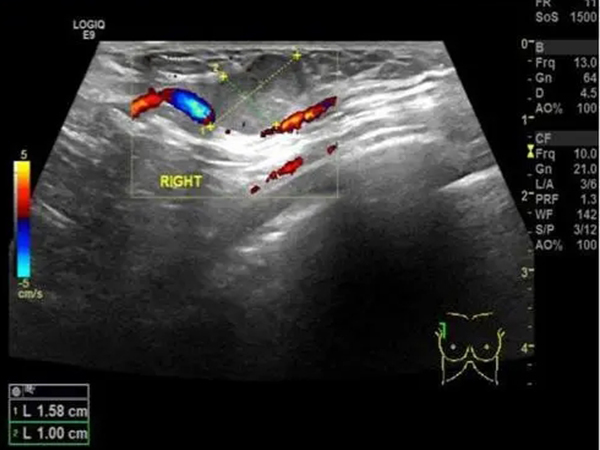

乳腺彩超全过程曝光,超声探头检查真的很简单

乳腺增生是女性常见的一种疾病,一般建议35岁以前的女性一年至少进行一次检查,而检查乳腺增生一般是通过乳腺彩超进行检查的,检查的流程十分简单,通常女性需平躺然后暴露..